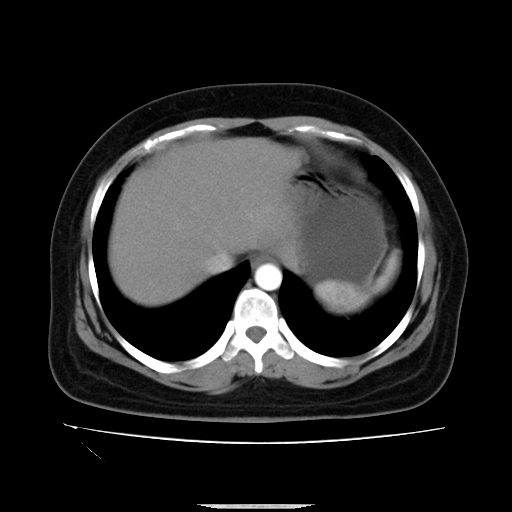

标题: CT14225:女性46岁。当地B超示肝内占位,来我院作CT检查。请 [打印本页]

标题: CT14225:女性46岁。当地B超示肝内占位,来我院作CT检查。请

速升速降,支持肝癌.脾体积增大,形态欠规整,请询问病史是否做过脾动脉栓塞.

右叶肝癌灶;慢性胆囊炎,不除外占位;;副脾可能性

肝内结节强化特点符合原发性肝癌表现,脾脏改变考虑为增大及先天发育所致。

动脉期病原灶明显强化高于肝密度且中央有无强化区,静脉期强化程度下降明显,延迟低于肝密度,考虑肝腺瘤可能性大,

符合肝癌表现,脾脏大(肝硬化?)

肝内结节强化特点:快进快出符合原发性肝癌表现

此患者虽然符合快进的特点,却不符合快出的特点,因为门脉期几乎是等密度,不符合肝癌的增强表现,所以我考虑肝局灶性结节增生可能性大

肝内结节强化特点符合原发性肝癌表现。脾大。

快进快出,符合肝癌表现。脾脏改变考虑为增大及先天发育所致。